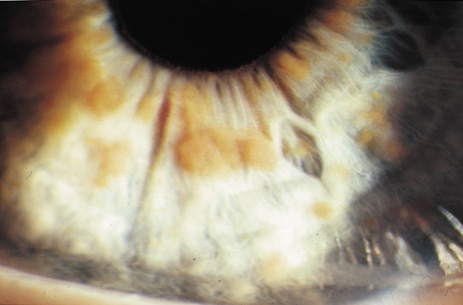

Cataracts in NF2 were recognized in 1986.97 They are common, reported to be found in 69%,98 81%,91 85%,99 and 87%100of cases. They are typically mild98 and a lens opacity may be the initial manifestation of disease, as found in 10% (5 of 49 patients) in one study.98

Retinal hamartomas affect about 10% to 20% of patients (8% in one study91and 22% in another98) and may be associated with a more severe phenotype of NF2.91,98 Combined pigment epithelial and retinal hamartomas (CPERH) and epiretinal membranes have been reported.101–103 Lisch nodules are rare in NF2. The absence of Lisch nodules, in association with the presence of posterior subcapsular or cortical cataracts (Fig. 8) may aid the differentiation of NF1 and NF2.97,104,105 Optic nerve sheath meningiomas may cause significant visual impairment in the first years of life (Table 2).84,106

Fig. 8. Neurofibromatosis type 2: cortical wedge cataract. Lens opacities (cortical wedge and posterior subcapsular cataract) may be the initial manifestation of disease in 10%.98